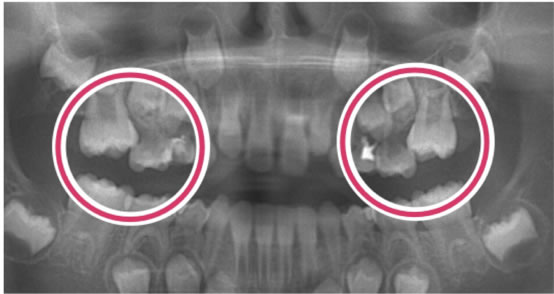

6歳臼歯(第一大臼歯)が手前の乳歯にひっかかっている状態。

奥歯が手前の乳臼歯にひっかかり、きちんと生えてこれない状態です。専門的には、第一大臼歯の「異所萌出」と言います。

上の6歳臼歯に多く、右左どちらかにだけ認められることが多いです。

① 乳臼歯が大きい

② 乳臼歯の後ろ、あるいは6歳臼歯の手前の形が膨らんでいる

③ 上顎歯列の幅が狭い

そのままにすると、6歳臼歯がさらに前に傾いて噛み合わせが悪くなります。また、虫歯になってしまう事があります。

引っかかる原因の乳臼歯を抜くと、6歳臼歯は前に寄りながら萌出してしまうので、抜いた乳臼歯の下にある永久歯が萌出するスペースが無くなってしまいます。

ブラケットを装着して、6歳臼歯を後ろに移動させ、萌出させる事です。状態によっては、他の方法もあります。

手間の乳臼歯は、根が溶けて吸収しているので、早く抜けてしまう事が多いです。そのような場合、せっかく良い位置に移動させた6歳臼歯が、再び手間に倒れてきてしまうので、保隙装置を装着する必要があります。

6歳臼歯の放出遅延をそのままにするとさらに前に傾いて

噛み合わせが悪くなります。

また、虫歯になってしまう事があります。

引っかかる原因の乳臼歯を抜くと、6歳臼歯は前に寄りながら萌出してしまうので、

抜いた乳臼歯の下にある永久歯が萌出するスペースが無くなってしまいます。